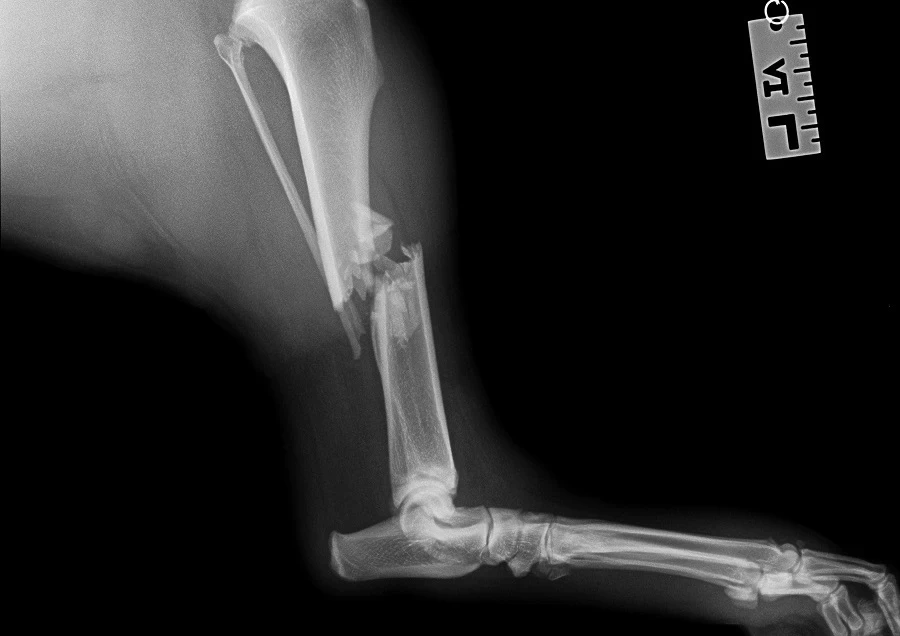

Trzyletni pies Reksio trafił do nas po 3 dniach od urazu, którego efektem było złamanie kości piszczelowej lewej. Złamanie zostało potwierdzone po…